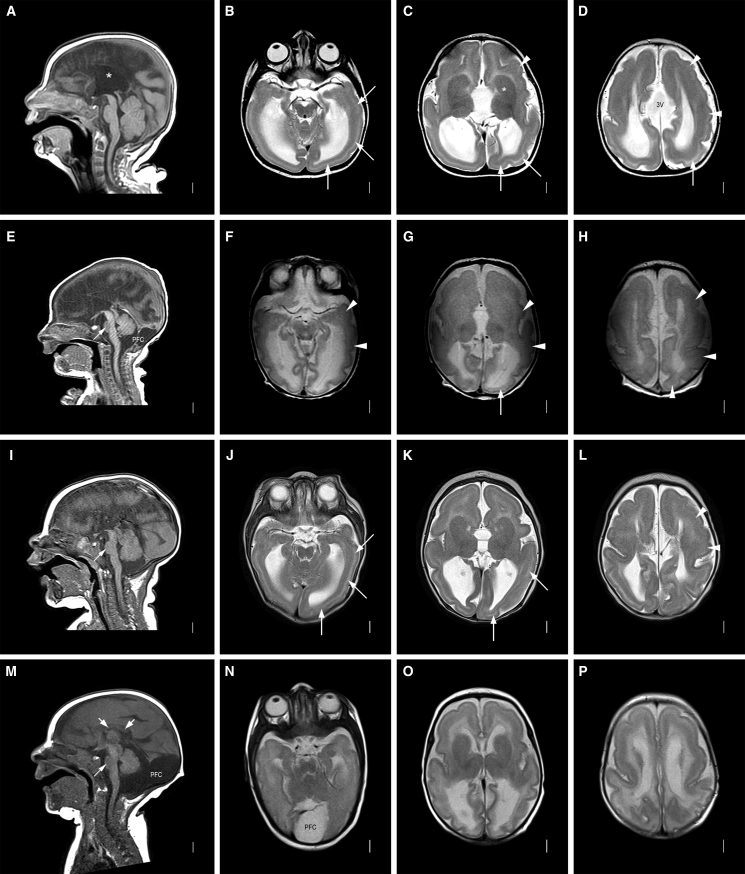

Figure 2.

Neuroradiology of affected individuals

Neuroimaging in four individuals with the CAMSAP1-related neuronal migration disorder (for further imaging see Figure S2): row 1 (A-D) is family 1, V:1 aged 7 months; row 2 (E-H) is family 2, II:1 aged 2 days; row 3 (I-L) is family 3, II:1 aged 3 months; row 4 (M-P) is family 4, II:1 aged 3 months. T1-weighted midline sagittal images show absent (∗ in A, also E and I) or short and thin (short white arrows in M) corpus callosum and small base of the pons (thin white arrow in E, I, and M). Enlarged posterior fossa or “mega cisterna magna” (PFC in E and M) was seen in 2/4 subjects. T2-weighted axial images show posterior-more-severe-than-anterior gradient with areas of agyria or severe pachygyria with prominent cell sparse zones and reduced thickness of the cerebral mantle/wall in posterior regions (white arrows in B–D, G, J, and K) and areas of less severe pachygyria with thicker cerebral mantle/wall in anterior regions (white arrowheads in C, D, F–H, and L). The gradient in family 4, II:1 (N–P) was less clear with lower resolution images. The boundaries of the basal ganglia and thalami were difficult to see, and the internal capsules are not seen (∗ in C, also in G, K, and O). The third ventricle was enlarged in all and dramatically enlarged into a midline interhemispheric cyst in family 1, V:1 (3V in D).

The neuroradiological abnormalities (Figure 2) are strikingly consistent across all of the affected individuals in this study. Affected individuals display a classic (thick) lissencephaly with P > A gradient. In posterior regions, areas of agyria or severe pachygyria with prominent cell-sparse zones and reduced thickness of the cerebral mantle/wall are seen, with areas of less severe pachygyria and thicker cerebral mantle/wall in anterior regions. Extra-cortical features include dysplasia of the hippocampus (short, globular, and under-rotated), basal ganglia, and thalami, alongside absence of internal capsule, an absent or extremely short and thin corpus callosum, mild-moderate brainstem hypoplasia, small base of the pons, severe underdeveloped frontal horn (likely due to the basal ganglia abnormalities), enlarged third ventricle, mild borderline enlarged tectum, and cerebellar hypoplasia, although the cerebellar folia pattern remains normal (within the limits of resolution). An enlarged posterior fossa or “mega cisterna magna” was also observed in 2/5 affected individuals (Table 1).